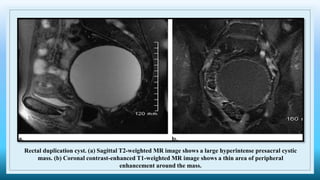

Rectal duplication cyst. (a) Sagittal T2-weighted MR image shows a large hyperintense presacral cystic

mass. (b) Coronal contrast-enhanced T1-weighted MR image shows a thin area of peripheral

enhancement around the mass.